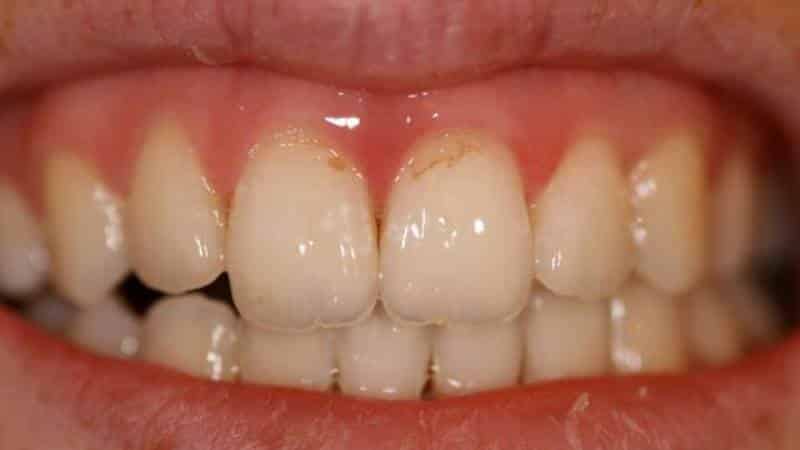

Одним из наиболее распространенных типов некариозных поражений является эрозия зубов. Она возникает в результате химического воздействия на зубную эмаль, часто вызванного кислотами, содержащимися в пище или напитках, а также в результате гастроэзофагеальной рефлюксной болезни. Клинически эрозия проявляется в виде гладких, блестящих участков на поверхности зубов, которые могут быть чувствительными к температурным изменениям и химическим раздражителям.

Еще одним видом некариозных поражений являются абразия и атрофия. Абразия зубов возникает в результате механического воздействия, например, из-за неправильной техники чистки зубов или использования жестких зубных щеток. Она проявляется в виде истончения эмали и образования вмятин на поверхности зубов. Атрофия, в свою очередь, связана с потерей твердой ткани зуба, что может быть вызвано различными факторами, включая возрастные изменения и недостаток минералов в организме. Клинически атрофия может проявляться в виде уменьшения высоты зуба и изменения его формы.